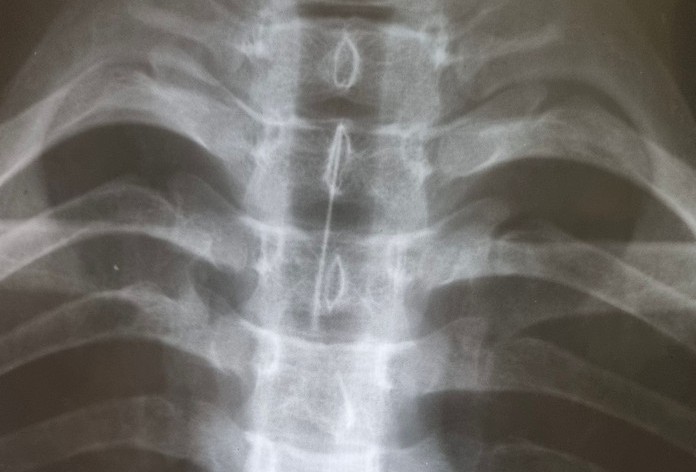

Накануне вечером 15-летний парень смотрел видео на компьютере и при помощи острого предмета решил достать частички пищи, застрявшие в зубах. В какой-то момент он засмеялся и вдохнул иголку. Подростка срочно доставили в больницу города Ангарска, где после рентген-исследования установили местонахождение опасного предмета. Игла с наконечником длиной пять сантиметров застряла в главном бронхе. Для извлечения инородного тела мальчика экстренно привезли в областной центр.

– Игла от шприца находилась в главном правом бронхе острием вверх. Захватить её удалось специальными щипцами «крысиный зуб». При контрольном осмотре признаков повреждения слизистой не обнаружили. Сейчас пациент находится под наблюдением врачей , – рассказала заведующая эндоскопическим отделением, хирург-эндоскопист, кандидат медицинских наук Анастасия Дмитриенко.